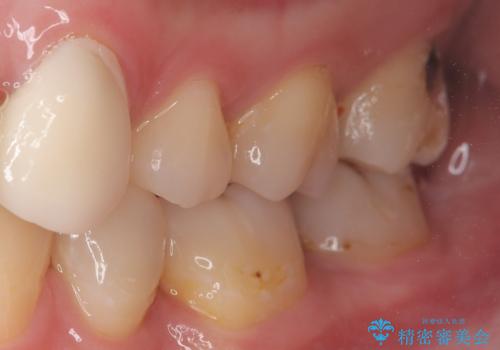

奥歯に虫歯があると言われた セラミッククラウンでキレイで長持ちする歯へ

担当医 榊原康平